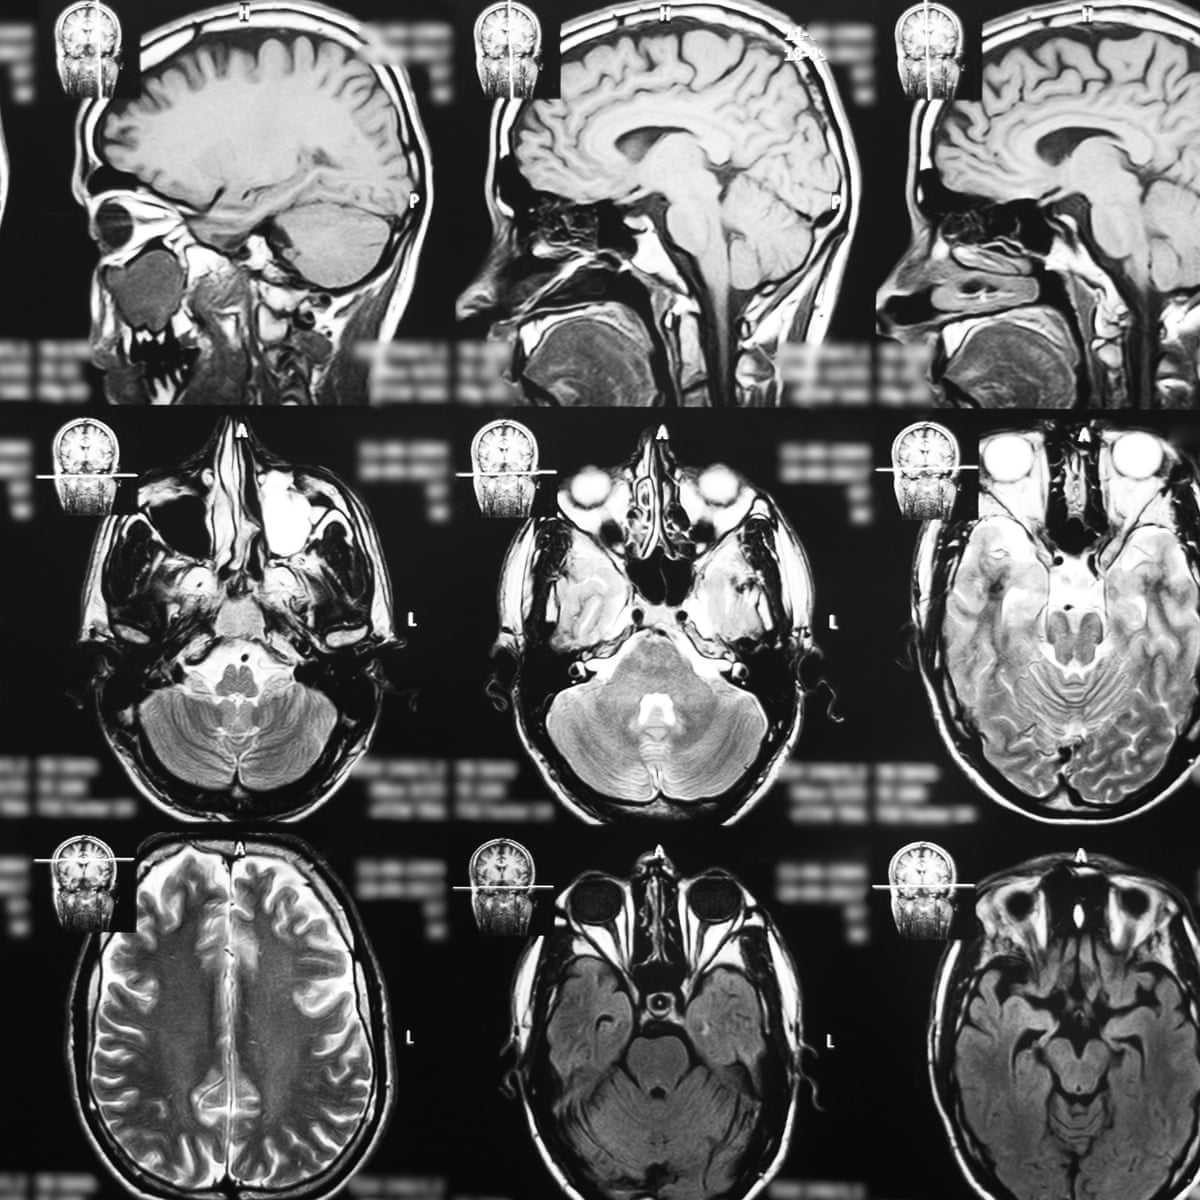

end stage glioblastoma patient

It has lots of info about endstage gbm including some symptom timelines. Glioblastoma GBM is also referred to as a grade 4 astrocytoma.

Diffusion Ring Enhancement Radiologia

Frontiers High Grade Glioma Treatment Response Monitoring Biomarkers A Position Statement On The Evidence Supporting The Use Of Advanced Mri Techniques In The Clinic And The Latest Bench To Bedside Developments Part 1 Perfusion